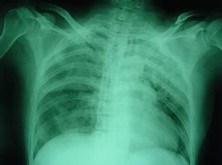

膈扑动(FlutteroftheDiaphragm)系指因膈肌阵发性或持续性痉挛,伴有吸气期声门突然关闭,产生一种短促奇特的声音、令人不能自制的一种症状。按痉挛轻重分为呃逆(Hiccup)、膈肌痉挛(Phrenospasm)、膈肌扑动。膈肌扑动少见,当其发作时,膈肌有极快的而有节奏的收缩,每分钟可达100~300次。... [详情]

• 发病部位在哪里?胸腔

• 应该做哪些检查项目呢?普通透视检查